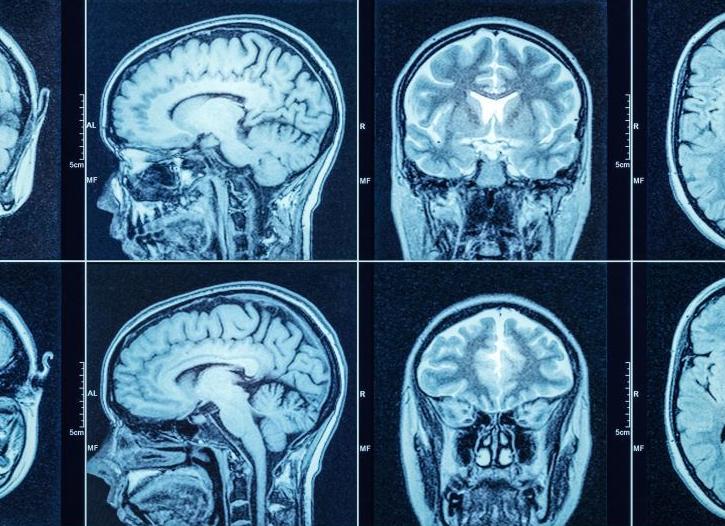

Компьютерная томография головы

Компьютерная томография области головы

КТ головы – это современный метод рентгенологического обследования, в ходе которого получаемые с аппарата данные обрабатываются компьютером. Послойные снимки хорошо визуализируют ткани головного мозга, сосуды, кости черепа и другие структуры головы. Сделать компьютерное исследование головы можно диагностических центрах, клиниках нейрохирургии и в профильных исследовательских институтах.